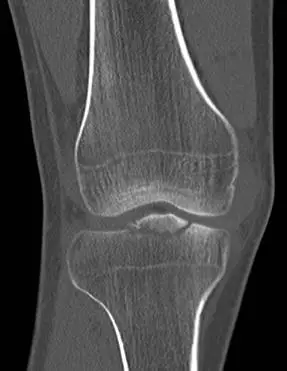

20歲男性病人因打球摔傷,膝部疼痛接受電腦斷層檢查,發現脛骨近端有骨折如圖。最可能合併下列何者傷害? 圖片描述 圖片描述

此題核心在於認識「Tibial eminence fracture(脛骨脊骨折)」即是前十字韌帶(ACL)於脛骨脊附著處之骨骼撕脫,為兒童與青少年特有的ACL等價損傷。

• 由矢狀面CT可見近端脛骨內、外側平台之間出現一塊線性骨片向前方偏移,骨片與平台底部仍以細小纖維連續,呈現典型的骨脊撕脫片段。

• 冠狀面CT顯示該撕脫片位於脛骨平台中央、略微向前凸出,並與髁間區保持一鉸鏈樣連接。

• 無明顯平台塌陷或關節面大範圍粉碎,提示為關節內骨折但屬撕脫型態。

本例為典型Tibial eminence avulsion fracture,專屬於ACL在脛骨脊附著處之骨撕脫。青少年運動傷害以韌帶附著處骨骼未完全骨化而先行撕脫最為常見。CT影像顯示中央部骨片向前偏移,正好吻合ACL撕脫機制;其他韌帶附著位置與本影像不符,故最佳選擇為前十字韌帶(ACL)合併損傷。